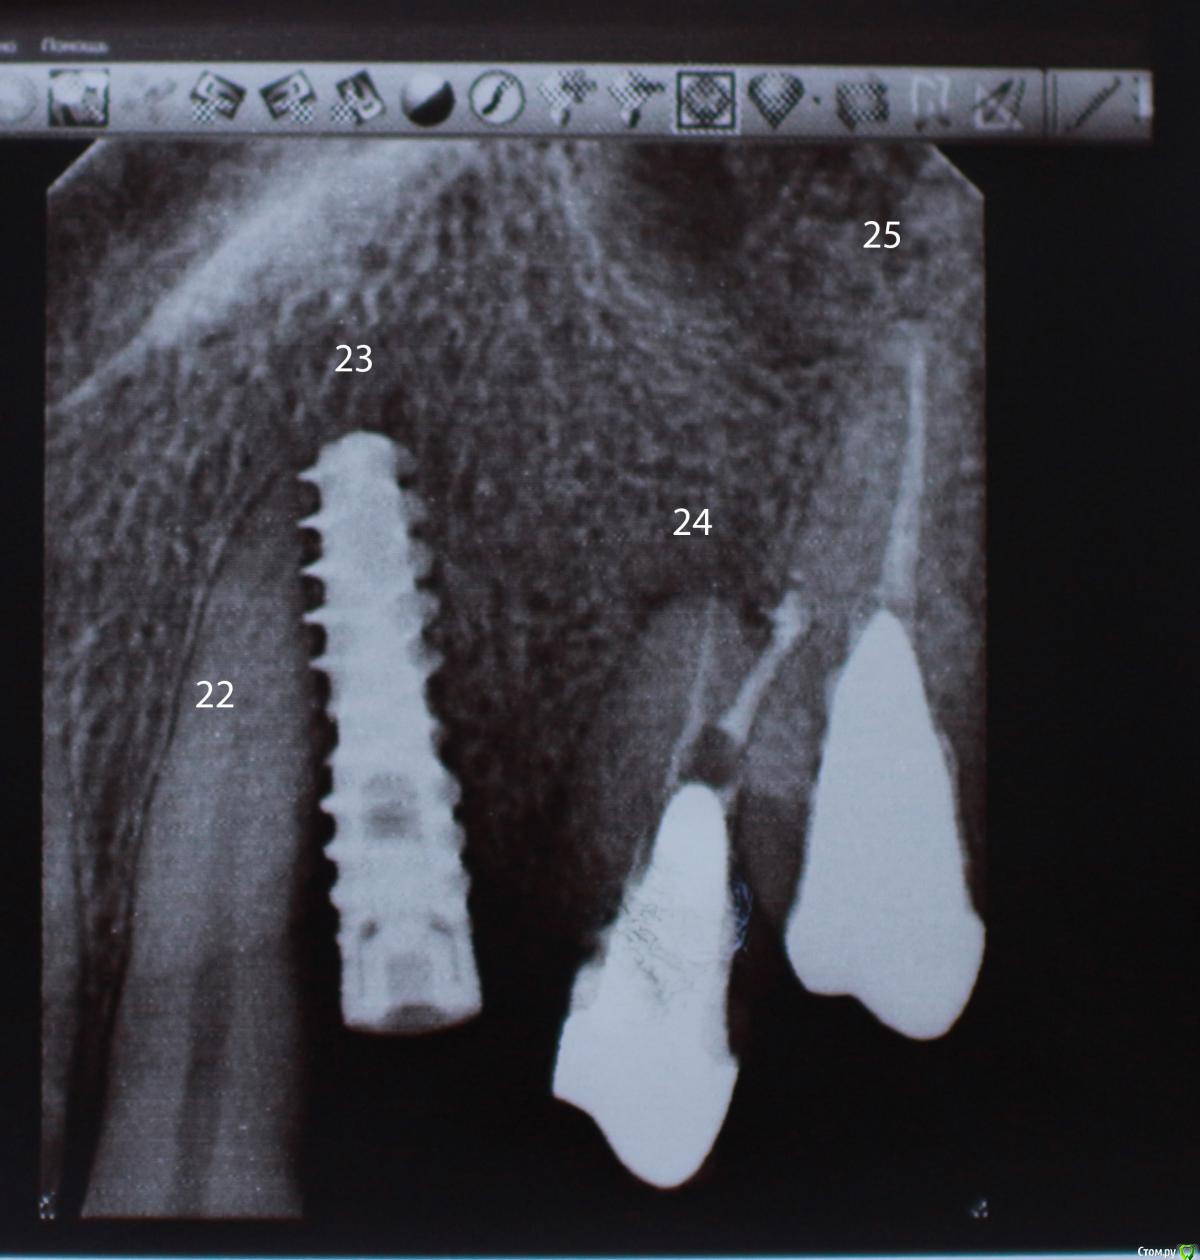

alex_ddd Опубликовано 28 июля, 2016 Автор Поделиться Опубликовано 28 июля, 2016 (изменено) Уважаемые господа! Спасибо за участие и отклики.Я только сейчас осознал, что запутался в номерах зубов и, вероятно, кропами фотографий сбил и вас с толку. Дело вот в чем: у меня на левой стороне верхней челюсти нестандартное расположение зубов - клык сразу идет вторым,3-ий , (где имплантант стоял до вчерашнего дня) это не выпавший молочный зуб.За ним идет 4-ый по счету, полагаю, вы говорите о нем. Его состояние плачевное? да?За ним 5-ка. Я ее депульпировал, потому что собирался ставить мост (жалею сейчас). Потом у меня нет нифига.. как видите, ну хоть синус лифтинг сделал на месте 6 И 7. Жду приживления.Я прикрепляю 2 фото, на нем я выставил номера. Если плох 24 зуб, что же мне следует предпринять? Заранее спасибо за ответы. да, с 2-й нет пока ясных ощущений, то ли чуть лучше, то ли так же.. Изменено 28 июля, 2016 пользователем alex_ddd Ссылка на комментарий

stommm Опубликовано 28 июля, 2016 Поделиться Опубликовано 28 июля, 2016 Можете попробовать сделать прицельный снимок зуба 24 (4-ка слева). Возможно там будет видно лучше. Если имеющийся снимок достоверен, то зуб скорее всего на удаление и имплантация 23, 24. Ссылка на комментарий